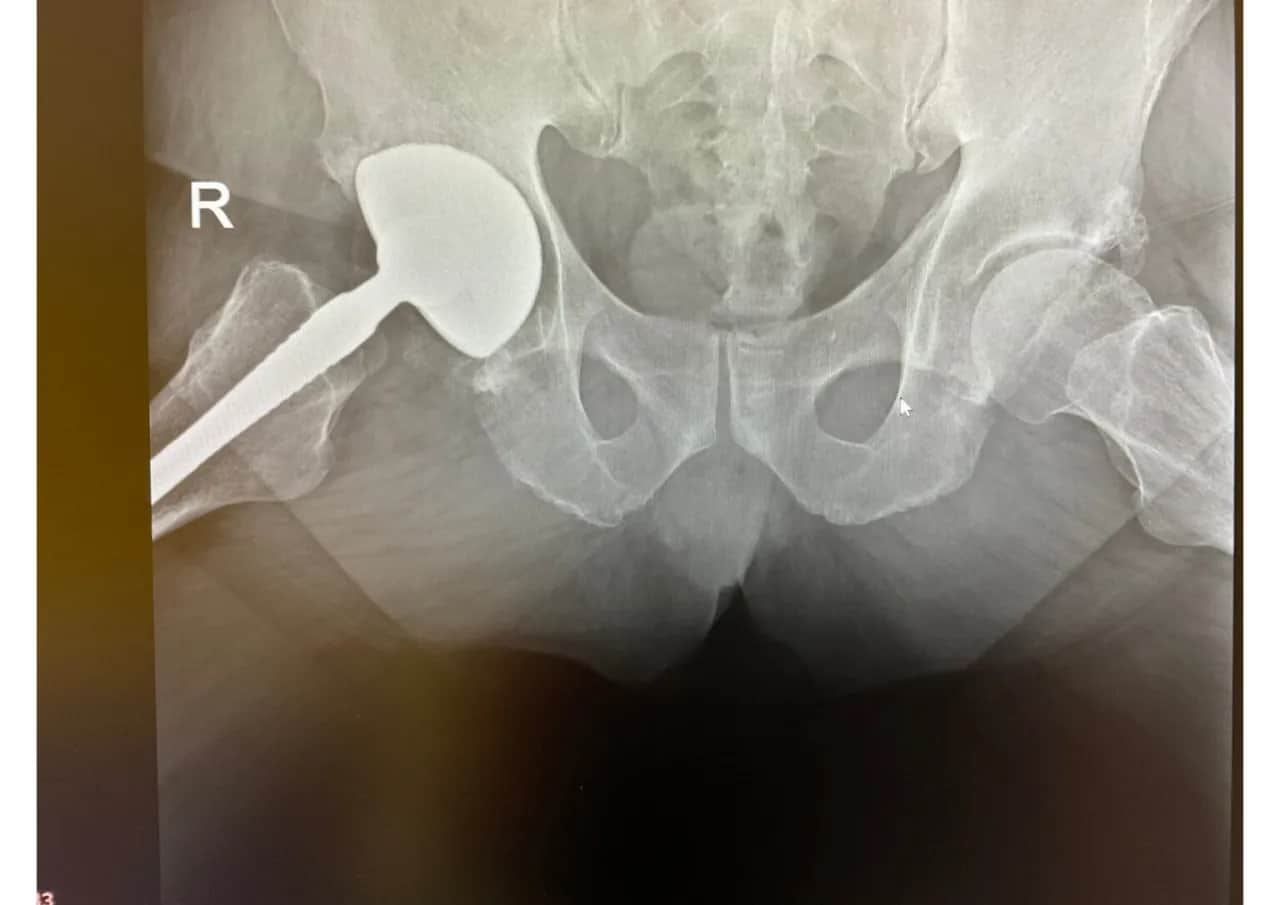

Ważne jest, aby pacjent miał przy sobie wszystkie niezbędne dokumenty, takie jak wyniki badań, zdjęcia rentgenowskie oraz historię medyczną. Przy wyborze specjalisty warto zwrócić uwagę na jego doświadczenie oraz opinie innych pacjentów. Wybór odpowiedniego lekarza może znacząco wpłynąć na jakość opieki oraz przebieg całego procesu leczenia.Proces uzyskiwania skierowania i wybór specjalisty